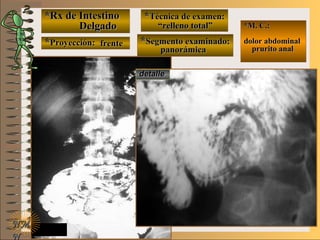

C-C-

**Segmento examinado:Segmento examinado:

*M. C.:*M. C.:

sin clínicasin clínica

NMNM

BBAA CC

E ME M

UNTUNT frentefrente

““relleno total”relleno total”

““mucosografía”mucosografía”

““doble contraste”doble contraste”

panorámicapanorámica

A-A-El examen es normal o patológico?El examen es normal o patológico?

Examen normal de estómago panorámico conExamen normal de estómago panorámico con

técnicas de : A- relleno total, B- mucosografíatécnicas de : A- relleno total, B- mucosografía

(tiene por objetivo reconocer el relieve interno(tiene por objetivo reconocer el relieve interno

grueso = a pliegues) y C- doble contraste (relievegrueso = a pliegues) y C- doble contraste (relieve

interno fino) en proyección de frenteinterno fino) en proyección de frente

B-B-Puede describir la o las imágenesPuede describir la o las imágenes

**OpciónOpción

de volverde volver